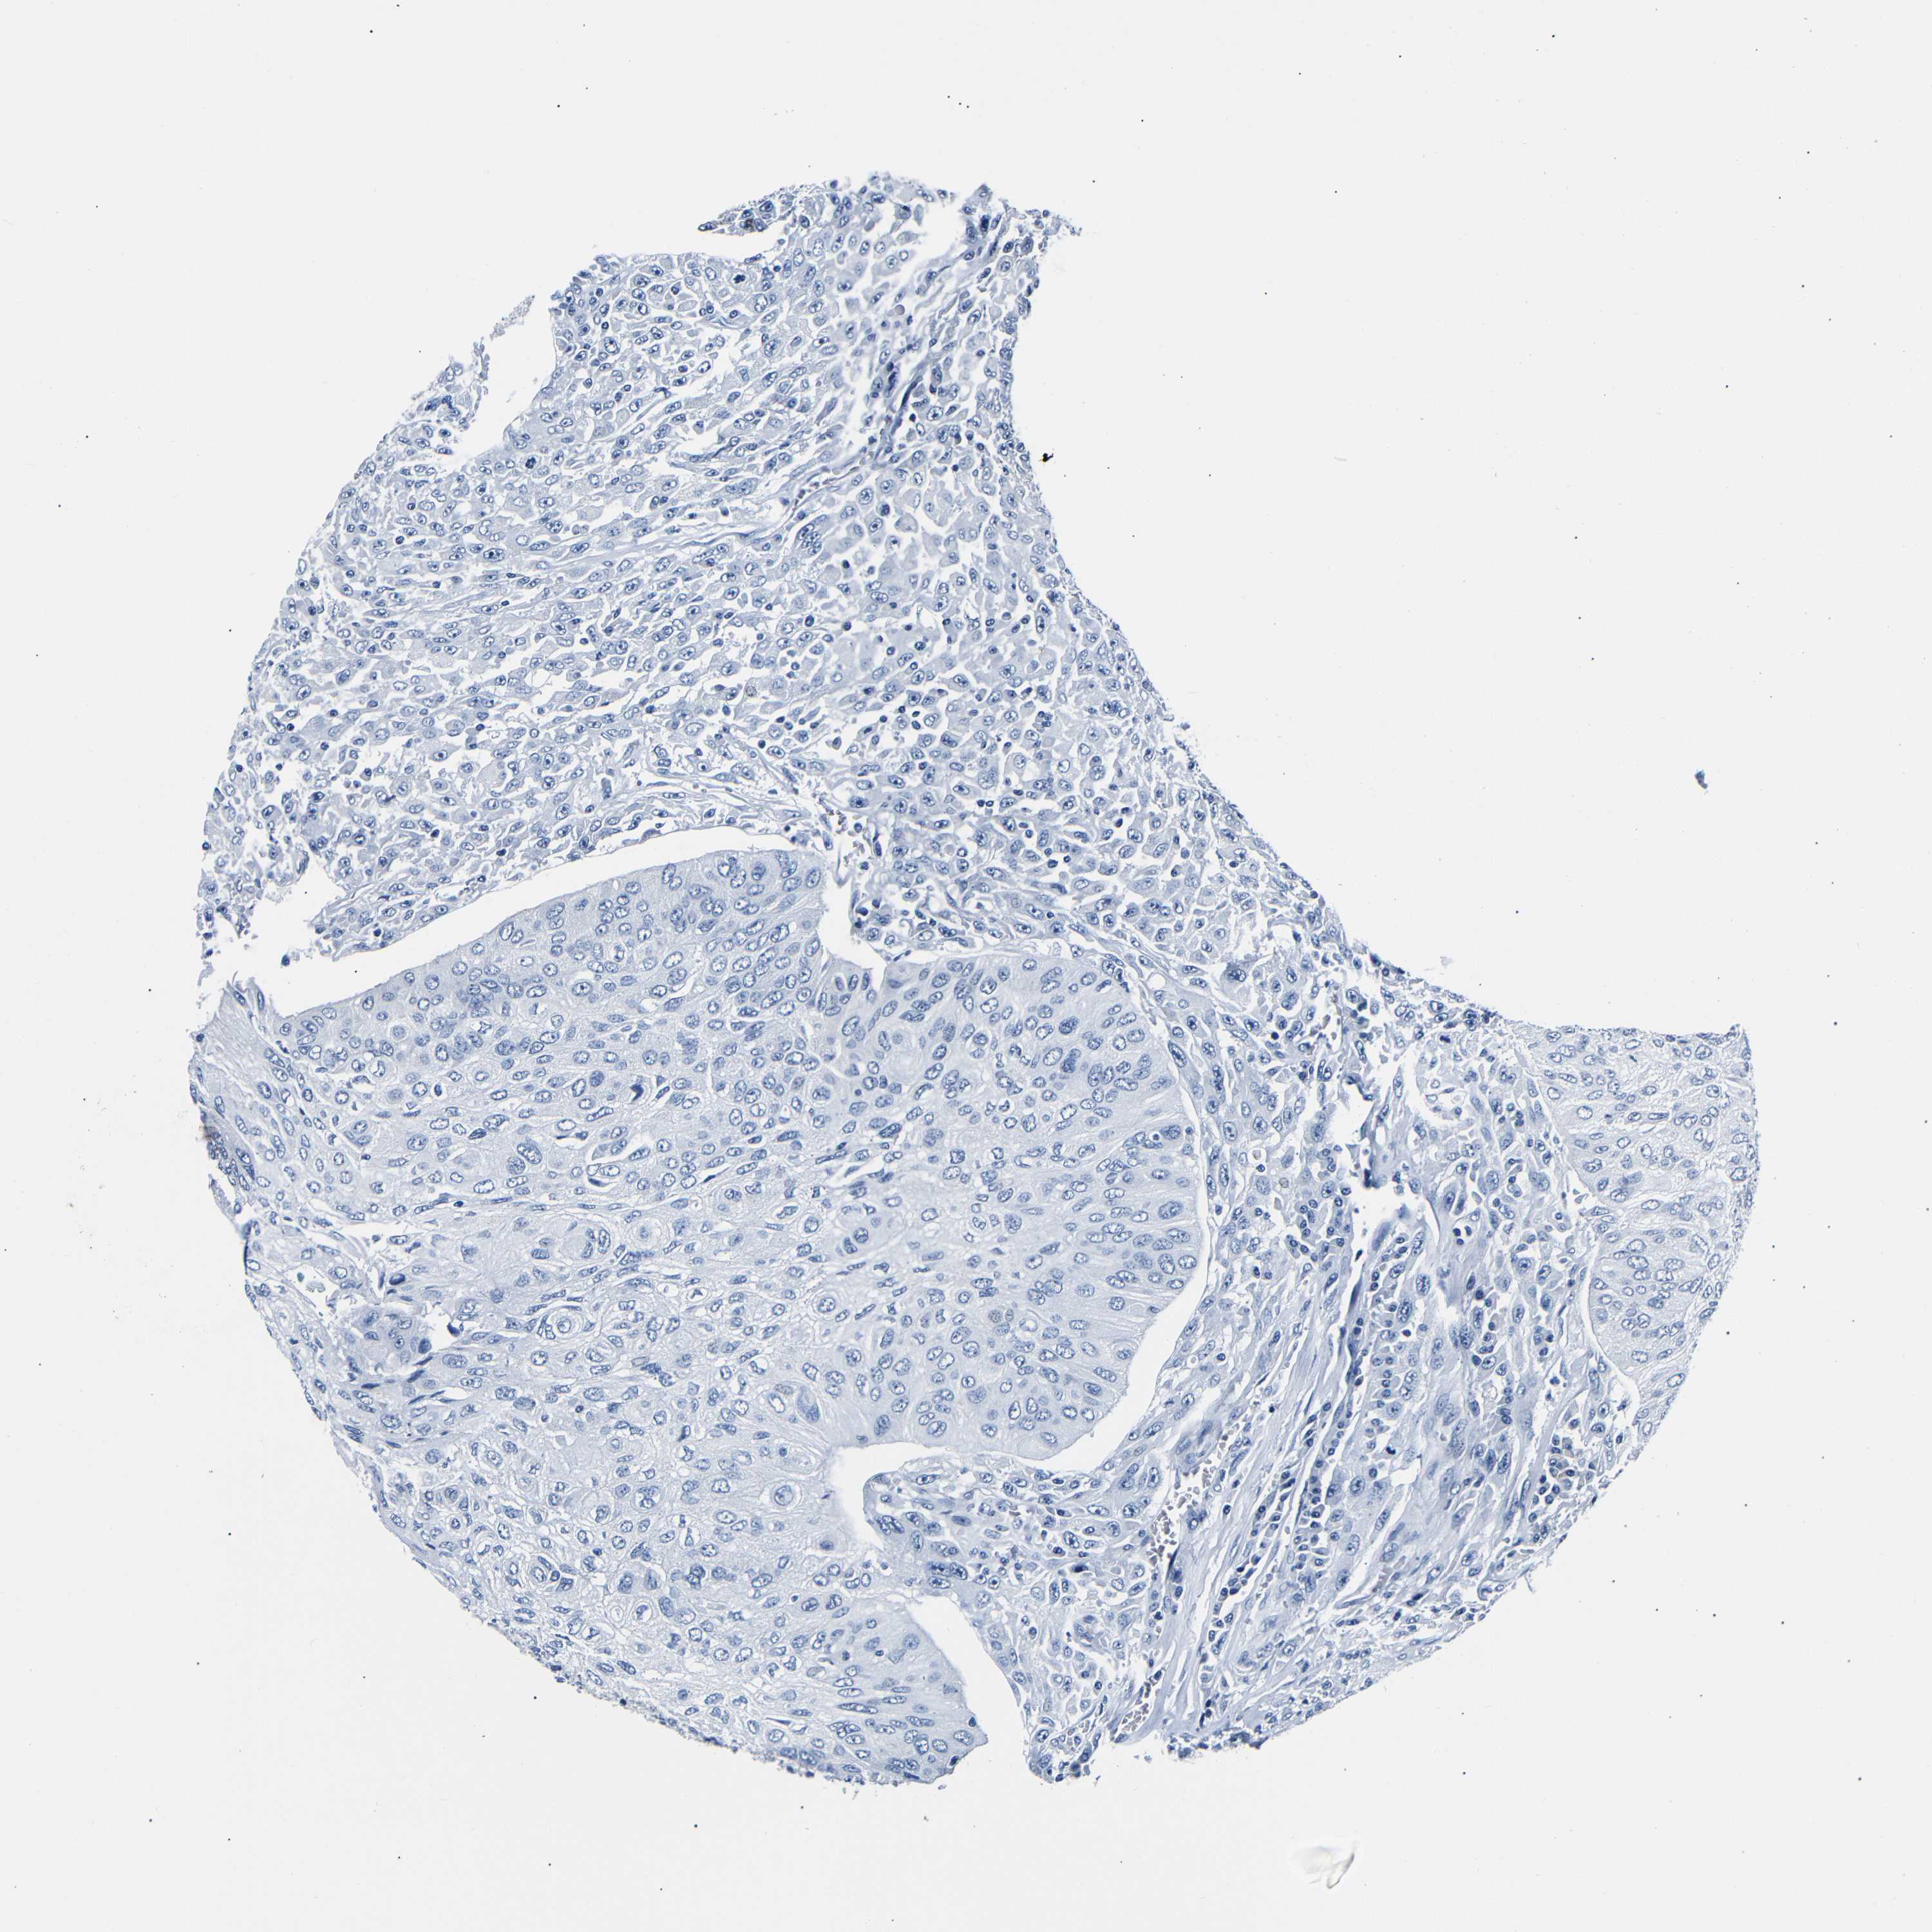

UROTHELIAL CANCER - Protein expressioni

A mouse-over function shows sample information and annotation data. Click on an image to view it in a full screen mode. Samples can be filtered based on level of antibody staining by selecting one or several of the following categories: high, medium, low and not detected. The assay and annotation is described here.

Note that samples used for immunohistochemistry by the Human Protein Atlas do not correspond to samples in the TCGA dataset.

Antibody stainingi

Antibody staining in the annotated cell types in the current human tissue is reported as not detected, low, medium, or high, based on conventional immunohistochemistry profiling in selected tissues. This score is based on the combination of the staining intensity and fraction of stained cells.

Each image is clickable and will lead to virtual microscopy that enables deeper exploration of all samples and also displays staining intensity scores, fraction scores and subcellular localization as well as patient and tissue information for each sample.

Antibody HPA013392

Antibody HPA015600

Antibody CAB004417

Staining

High

Medium

Low

Not detected

Intensity

Strong

Moderate

Weak

Negative

Quantity

>75%

75%-25%

<25%

None

Location

Nuclear

Cytoplasmic/membranous

Cytoplasmic/membranous,nuclear

Urothelial carcinoma, Low grade

Urothelial carcinoma, High grade